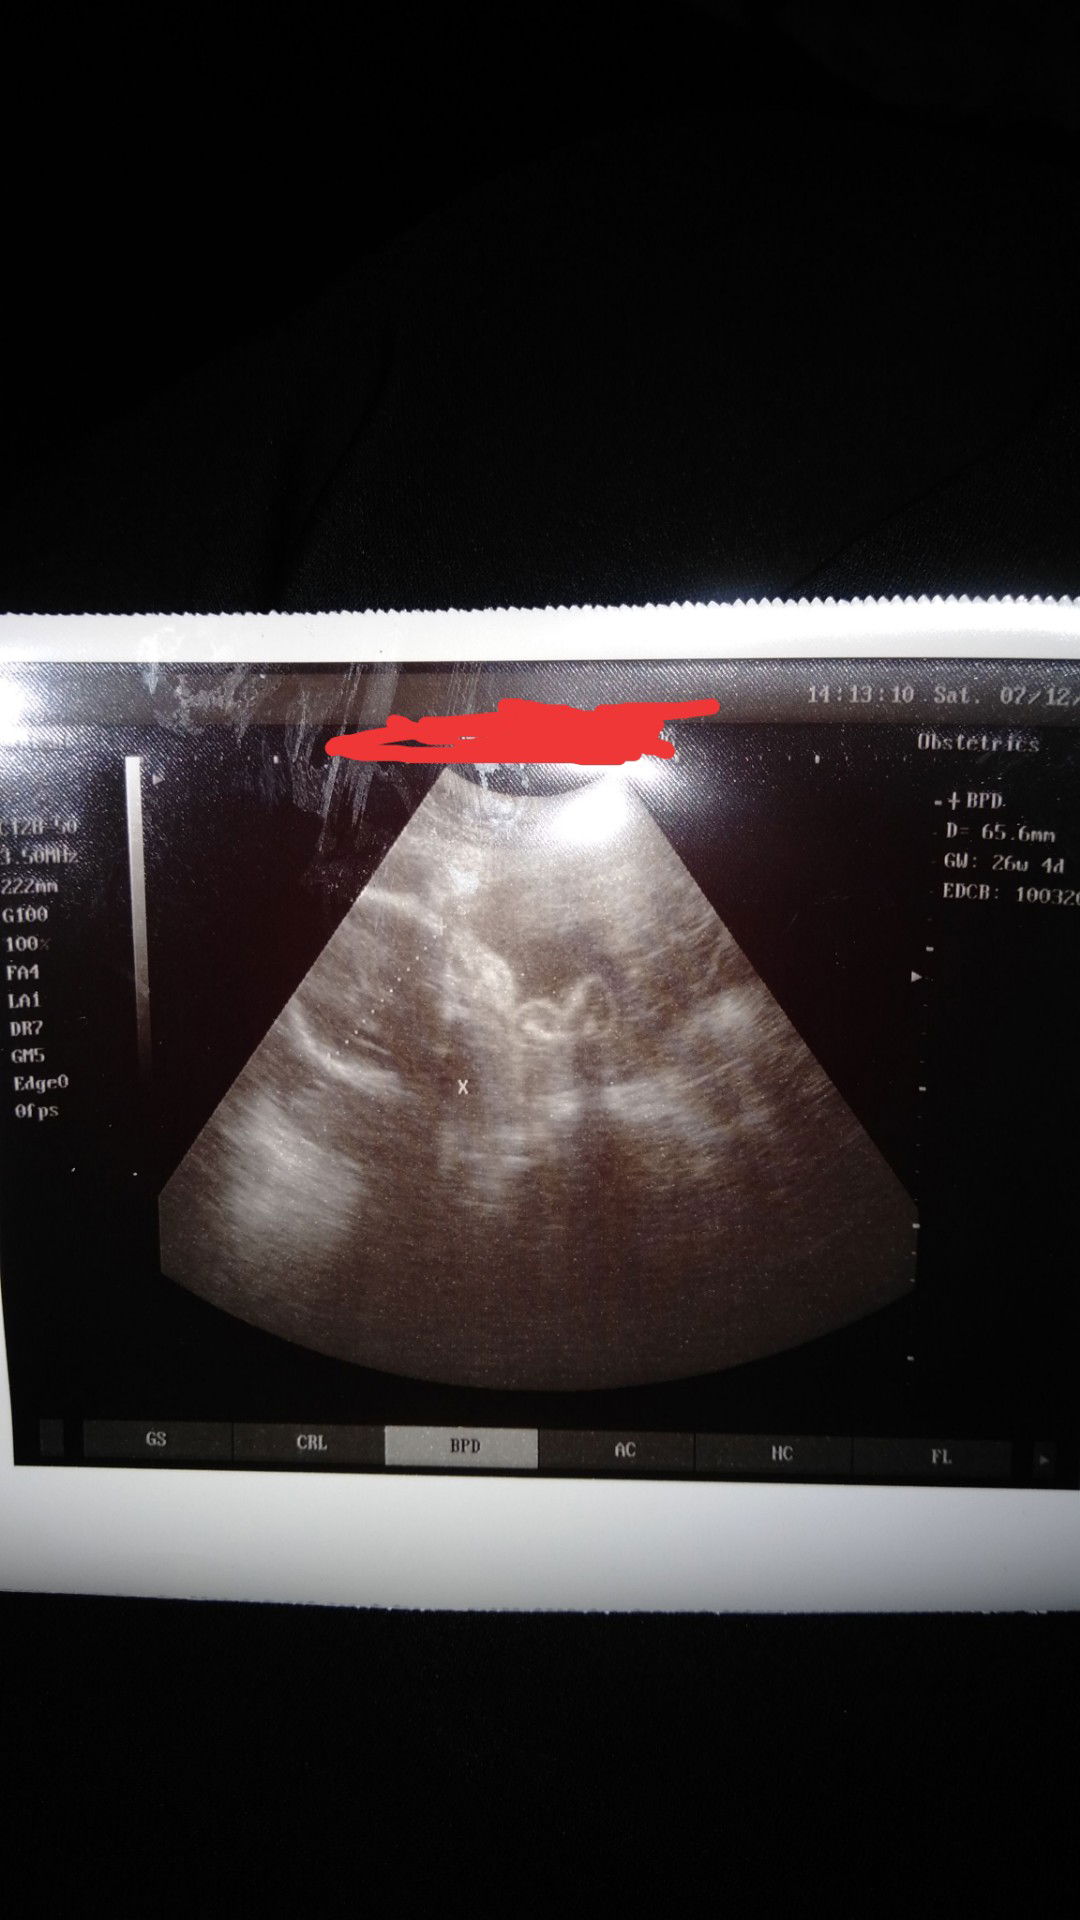

Assalamualaikum Bun.. sedikit curhat Bun.. Semalam aku dri dokter trus d USG lah tuh..sebelnya dokternya terburu2 bnget bun..pdhal rencananya periksa in skalian mo Thu jnis kelamin nya..eh boro2 mo tnya it..mo tnya BB-nya aja langsung d potong SMA dokternya..tuh alat nempel d perut ngak smpe 30 detik..dia udah blg kepala udah di bawah trus d ukur langsung deh tuh foto d print..selesai..? pdhal aku tuh msh MW tnya2.. plasenta nya gimana..jknya apa..sebel bnget bun..trus pas aku tuna BB-nya Dy jwab msh kecil..?? D sini ad ngak yg bisa BCA hasil USG ngak untuk Thu BB nya bayiku berapa Bun??..kira2 klu aku MW USG LG d tempat lain beberapa hari kedepan nda masalah kah Bun?? Mohon sarannya..